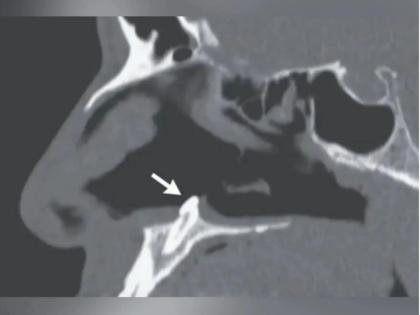

डॉक्टरांनी या व्यक्तीची rhinoscopy केली आणि रिपोर्ट पाहून तेदेखील थक्क झाले. रायनोस्कोपी ही एक अशी प्रक्रिया आहे ज्यात रुग्णाच्या नाकाची तपासणी करण्याकरता त्यात एक ट्यूब टाकली जाते. ट्यूबमध्ये कॅमेरा लावल्यानंतर समजलं की या व्यक्तीच्या नाकाच्या आतमध्ये एक पांढऱ्या रंगाचा अवयव वाढत आहे. तपासात समजलं की तो एक अॅक्टोपिक दात आहे. अॅक्टोपिक दात म्हणजे चुकीच्या ठिकाणी उगवलेला दात. ही अतिशय दुर्मिळ स्थिती असते.

जर्नलमध्ये सांगितलं गेलं की दात ओरल आणि ओटोलॅरिनगॉलोगिक सर्जरीच्या माध्यमातून काढण्यात आला (Doctors Removed Tooth from Nose). याची लांबी १४ मिलीमीटर होती. सर्जरीनंतर तीन महिन्यांनी रुग्णाला चेकअपसाठी बोलावलं असता समजलं की त्याची श्वास घेण्यात येणारी समस्याही बंद झाली आहे. रिपोर्टमध्ये सांगितलं गेलं की अनेकदा दात व्यवस्थित उगवत नाहीत आणि ते जबड्यातच रोवले जातात. त्यामुळे ते वेगळ्याच दिशेने उगवू लागतात आणि याच परिस्थितीत या व्यक्तीप्रमाणे अवस्था होते.